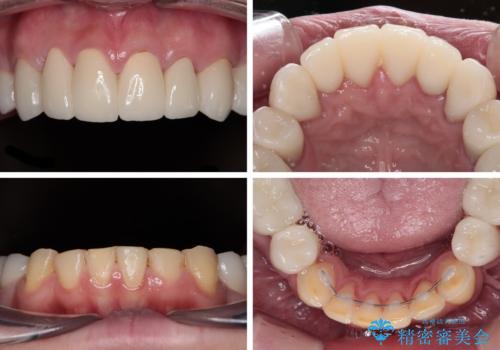

酸蝕歯でボロボロの歯の審美歯科治療 矯正治療も併用して、美しい口元へ

- 一時期の拒食症に伴い歯が酸で溶けてボロボロになってしまったとのことで来院された患者様です。

酸によりエナメル質の大半が溶けており、下顎前歯以外は酷いむし歯のような状態でした。

当初はほとんどの歯をむし歯治療のようにオールセラミッククラウンにて補綴治療を行う予定でしたが、仮歯に置き換えた時点で、口元の突出感や下顎前歯の叢生が気になるとのことで、上下左右の第一小臼歯4本を抜歯したワイヤー装置での抜歯矯正を行うこととしました。

矯正治療終了後に、残った歯をオールセラミッククラウンにて補綴治療を行うこととしました。

途中来院が困難な時期があったり、歯周外科処置を行って治癒を待ったりと、治療期間は長くなりましたが、初診時とは比べものにならないくらいきれいに仕上げることができました。